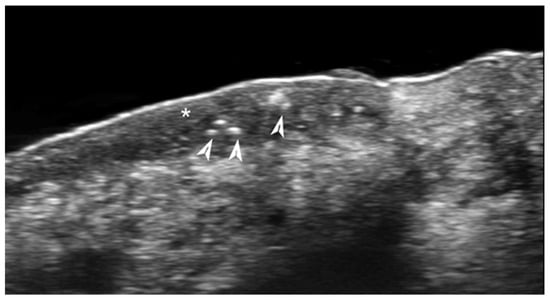

- Sechi, A.; Patrizi, A.; Vincenzi, C.; Savoia, F.; Tartari, F.; Leuzzi, M.; Di Altobrando, A.; Besagni, F.; Merli, Y.; Neri, I. Sonographic features of vaccination granulomas in children with delayed-type hypersensitivity to aluminum. Pediatr. Dermatol. 2019, 36, 1012–1016. [Google Scholar] [CrossRef]